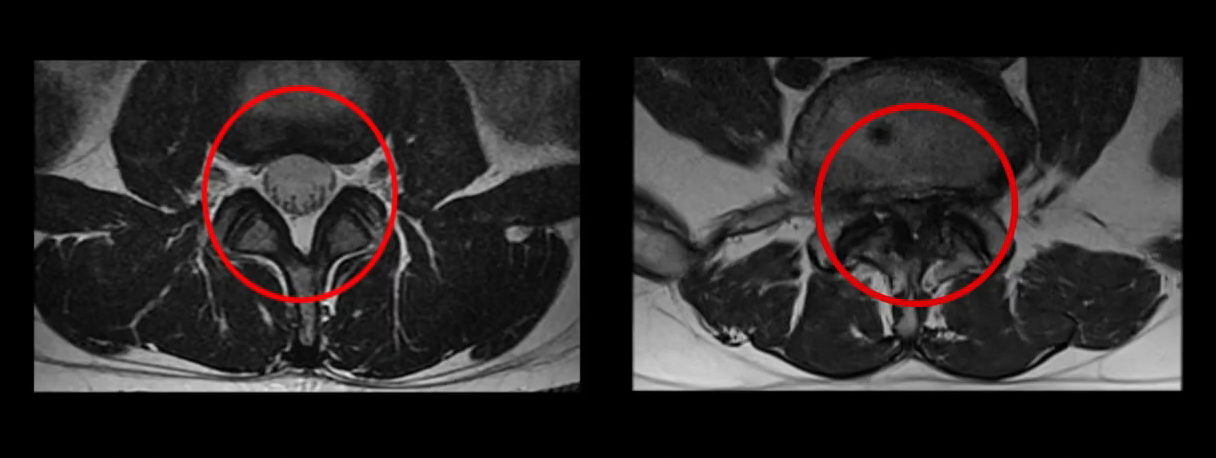

여기 MRI 화면을 보고 설명 드리겠습니다. 척추관협착증 환자의 MRI입니다. 척추를 이렇게 잘라서 보는 겁니다. 왼쪽의 정상적인 척추관에 비해 오른쪽의 협착이 있는 척추관은 척추뼈, 척추후관절, 인대, 디스크 등 척추구조물들의 퇴행성 변화로 인해 척추 신경다발이 지나가는 통로인 척추관이 좁아지면서 신경다발이 전체적으로 눌려 있는 모습입니다.

추간공협착증 환자의 MRI입니다. 척추를 이렇게 옆으로 잘라서 보는 겁니다. 척추 신경다발에서 갈라져 빠져 나온 신경가지 하나가 지나가는 구멍을 추간공이라고 하는데 여기 보이시는 것처럼 이 추간공이 좁아져 신경가지 하나가 눌려 있는 모습입니다.

즉, 쉽게 말해 척추관협착증과 추간공협착증은 주관이 좁아져 전체 신경다발을 누르느냐, 보조관이 좁아져 신경가지 하나를 누르느냐의 차이가 있습니다. 비유하자면 척추관협착증은 고속도로가 막힌 것이고 추간공협착증은 고속도로에서 빠져 나가는 출구가 막힌 것입니다. 그래서 사실 추간공협착증은 어떤 특정 신경가지 하나가 눌리는 것이기 때문에 디스크와 매우 비슷한 질환이라고 볼 수 있으며, 그래서 척추관협착증에 비해 통상적으로 재활치료가 훨씬 더 쉽고 치료 후 결과도 좋은 편입니다. 여러분들도 협착증과 디스크, 두 질환을 놓고 봤을 때 협착증보다 디스크 치료가 훨씬 더 쉽다는 걸 잘 알고 계실 겁니다.